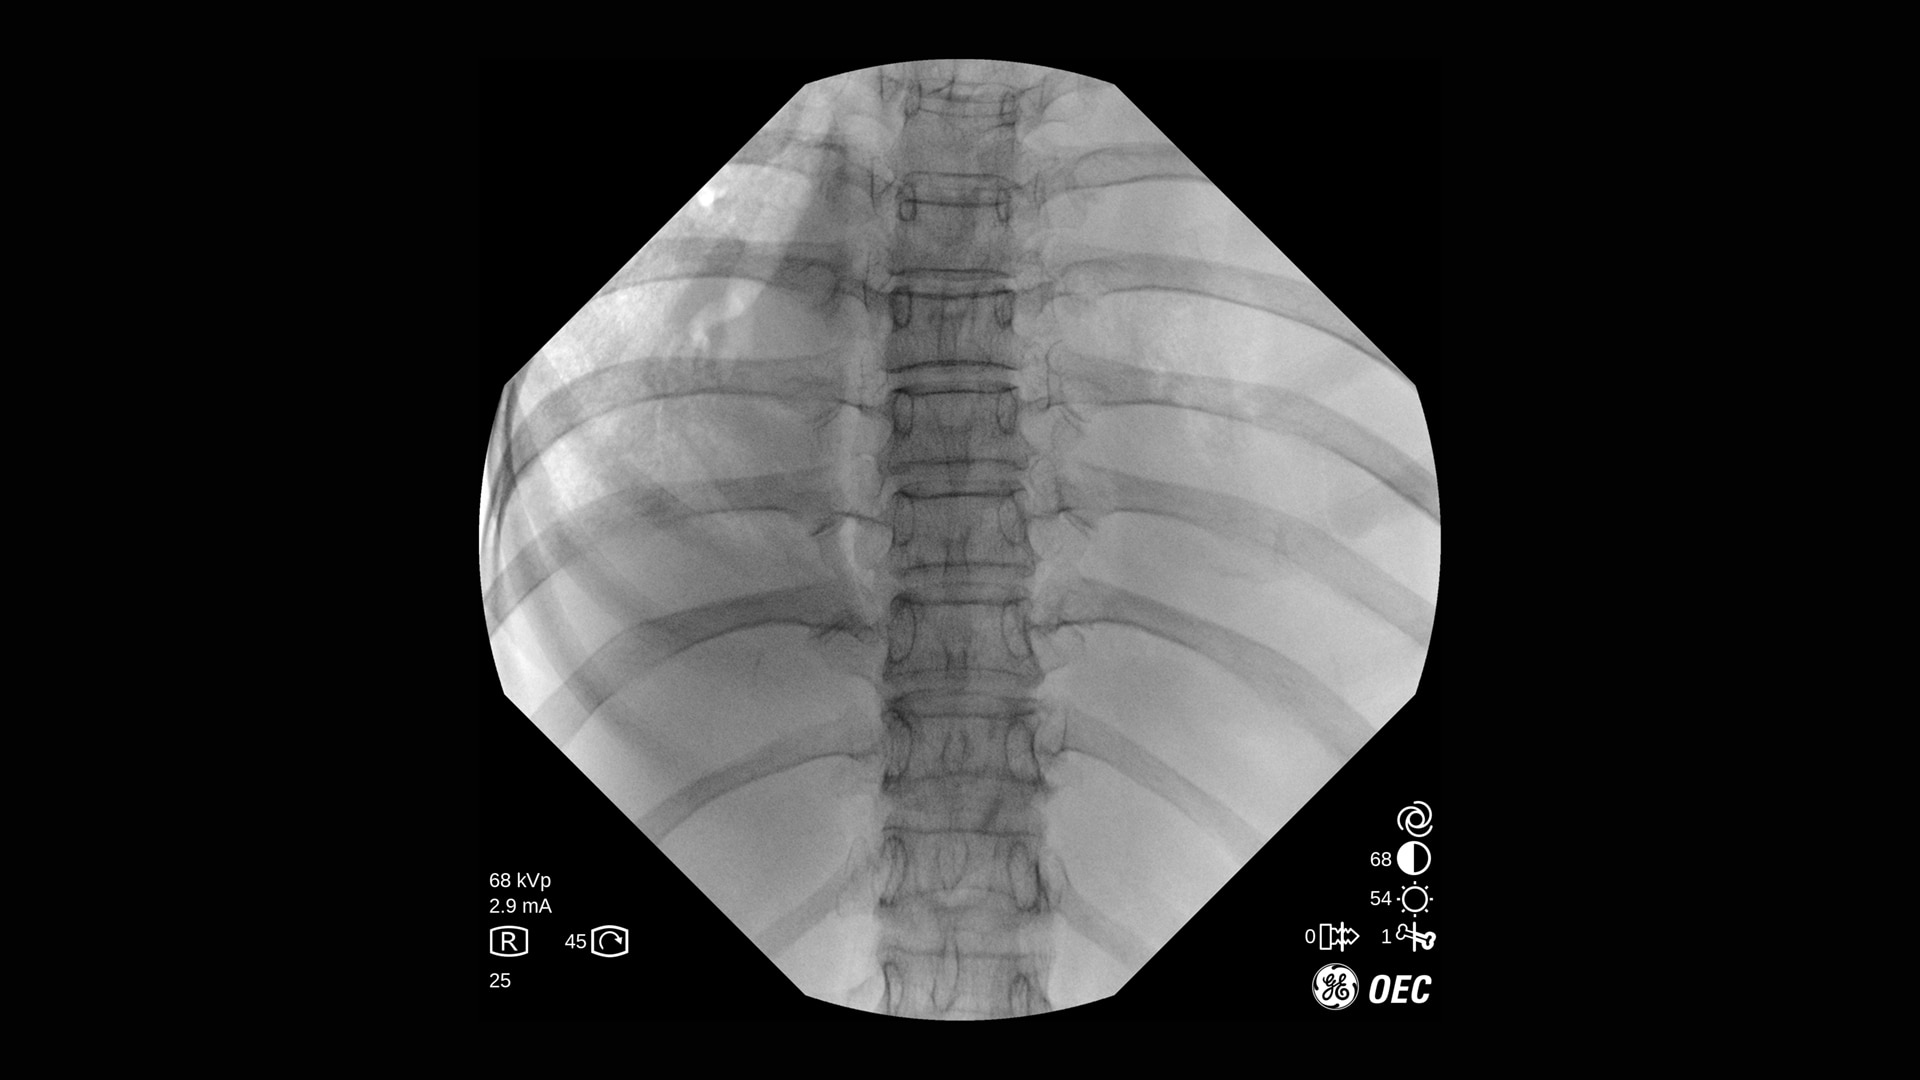

Der OEC One CFD unterstützt ein breites Spektrum klinischer Anwendungen: von endoskopischen Interventionen und Schmerztherapie bis hin zu komplexen Wirbelsäulen- und orthopädischen Verfahren.

Die Bildqualität ist bei verschiedenen Verfahren und Verfahrenseinstellungen essenziell, besonders auf engem Raum. Mit OEC One CFD erleben Sie die Bildqualität, die sie von den OEC mobilen C-Bögen erwarten, sowie die klinische Vielseitigkeit, die bei einem mobilen All-in-One-C-Bogen mit zwei Detektorgrößen benötigt wird.

Der OEC One CFD liefert gestochen scharfe Bilddetails – erfasst mit einem Flat-Panel-Detektor und dargestellt auf einem 27" 4K-UHD-Monitor direkt am OP-Feld.

Optimieren Sie Bildqualität und Dosis mit Live-Zoom, Adaptive Dynamic Range Optimization (ADRO), Bewegungsartefakt-Unterdrückung und weiteren intelligenten Bildverarbeitungsfunktionen.

Mit der Point-and-Shoot-Funktion (automatische Anpassung der Bildparameter) des OEC One CFD erfassen Sie Bilder schnell und einfach – ideal für Anwendungen von der Orthopädie bis zur peripheren Gefäßchirurgie.